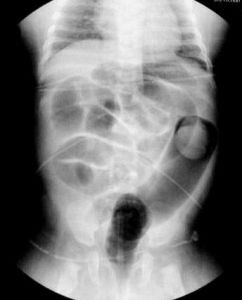

2.空氣灌腸

在空氣灌腸前先作腹部正側位全面透視檢查,觀察腸內充氣及分布情況。注氣後可見在套疊頂端有緻密軟組織腫塊呈半圓形,向結腸內突出,氣體前端形成明顯杯口影,有時可見部分氣體進入鞘部形成不同程度鉗狀陰影。診斷明確的同時也可加壓進行復位治療。